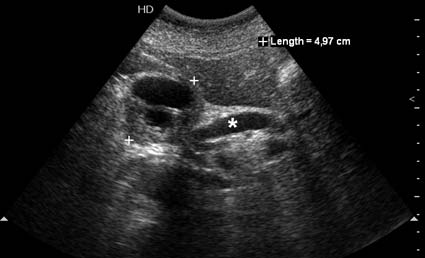

Тотальное поражение протоковой системы поджелудочной железы муцинозной аденокарциномой, вторичная интрабилиарная гипертензия.Клинически должна быть еще выраженная экзокринная недостаточность

Коллеги, восхищен вашими ответами. Уже много лет работаю в хирургической клинике, но проблема диагностики рака панкреас, дифференциальной диагностики с псевдотуморозным панкреатитом для меня остается актуальной. Ведь очень часто мы даже не видим опухоль даже на неплохом по качеству ультразвуковом оборудовании. Что может помочь в диагнозе?

Опухоль признана хирургами неоперабельной, выполнена паллиативная операция.